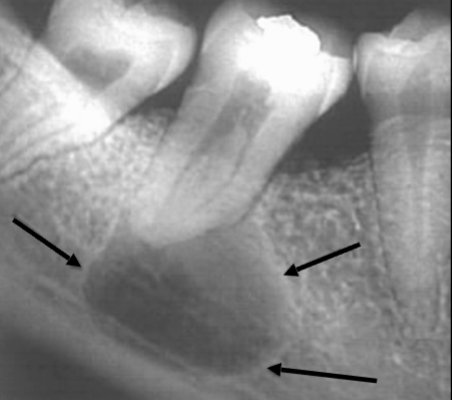

Describe the radiographic features of this Buccal Bifurcation Cyst?

Buccal Bifurcation of Molars

Roots Displaced Lingually

Occlusal Plane Inclined Buccally

Lingual Cusp Higher on BWs and PAs